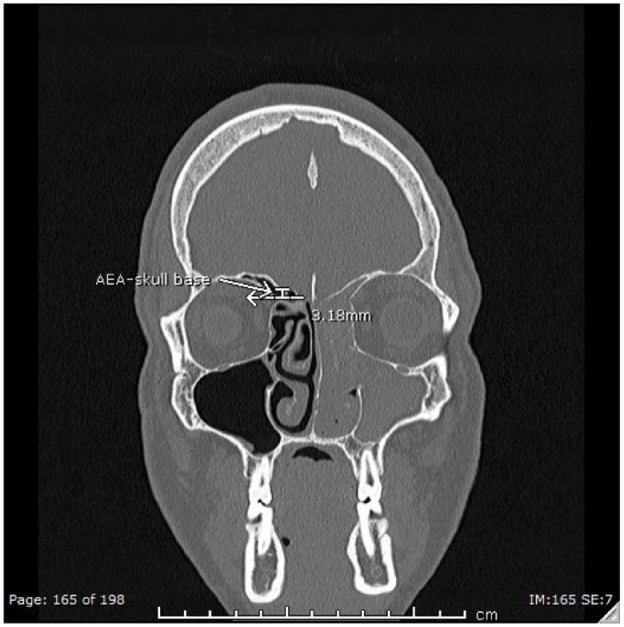

Objectives: Allergic fungal rhinosinusitis (AFRS) often results in expansion of disease beyond the paranasal sinuses, which may put important structures, such as the anterior ethmoid artery (AEA) or lateral lamella of the cribiform, at risk of injury during endoscopic sinus surgery (ESS). This study aims to compare the AEA to skull base (AEA-SB) length in patients with AFRS versus chronic rhinosinusitis with nasal polyps (CRSwNP), as well as additional anatomic variants.

Methods: A single institutional retrospective chart review of patients undergoing ESS for AFRS and CRSwNP was performed. AEA-SB length were compared between the 2 groups. Other anatomic variants, including Keros measurement and presence of supraorbital ethmoid air cells (SOEC), concha bullosa (CB), sphenoethmoidal, and infraorbital ethmoid cells were measured and compared between the 2 groups.

Results: Twenty-one patients were included in each cohort. The AFRS group was younger in age (P = .015) and had a significantly longer AEA-SB length (P = .014) compared to the CRSwNP group. No significant differences were observed between the 2 groups regarding Keros measurement, presence of concha bullosa, infraorbital ethmoid, sphenoethmoidal, or SOEC. No association was seen between AEA-SB length and Keros class in either group.

Conclusions: AFRS harbors anatomical differences when compared to CRSwNP, with the former associated with a longer AEA-SB length. This key difference should be considered in preoperative planning to prevent injury to the AEA in patients undergoing ESS for AFRS.